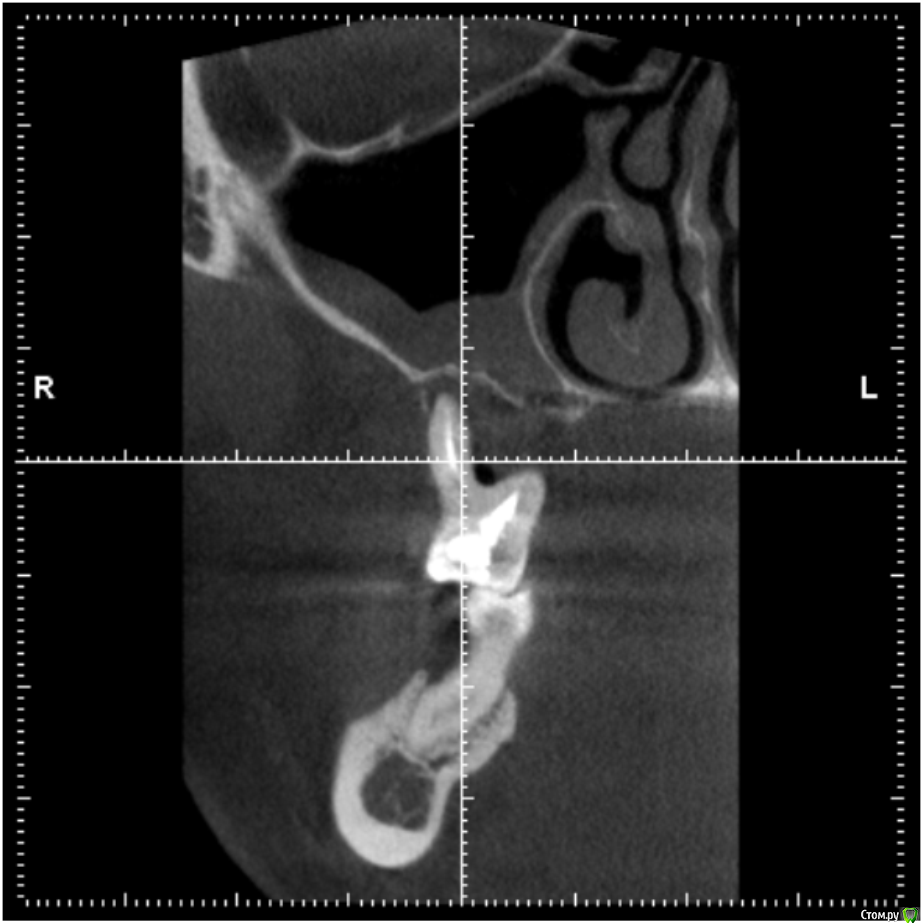

Pacient1234 Опубликовано 26 апреля, 2017 Поделиться Опубликовано 26 апреля, 2017 Уважаемые профессионалы, подскажите пожалуйста.Проблема: тяжелый хронический пародонтит, шатаются жевательные верхние зубы (зашинированы). По результатам КТ – отсутствие костной ткани на этом участке. Из-за этого хирург-имплантолог сказал, что мне нельзя делать ни синус лифтинг, ни имплантацию – бесполезно, имплантаты в итоге не приживутся, только выброшу деньги на ветер. Честно говоря, меня это слегка озадачило.. Действительно ли такое может быть, что костная ткань отсутствует настолько, что никакие методы ее нарастить невозможны (или возможны, но есть большая вероятность, что не получим положительный результат имплантации)?Еще больше меня волнует вопрос, как будет дальше развиваться моя ситуация. Как я понимаю, рано или поздно шатающиеся зубы выпадут и меня ждет съемный протез. Что при этом будет происходить с костной тканью? Какие риски такой стратегии?Спасибо! Ссылка на комментарий